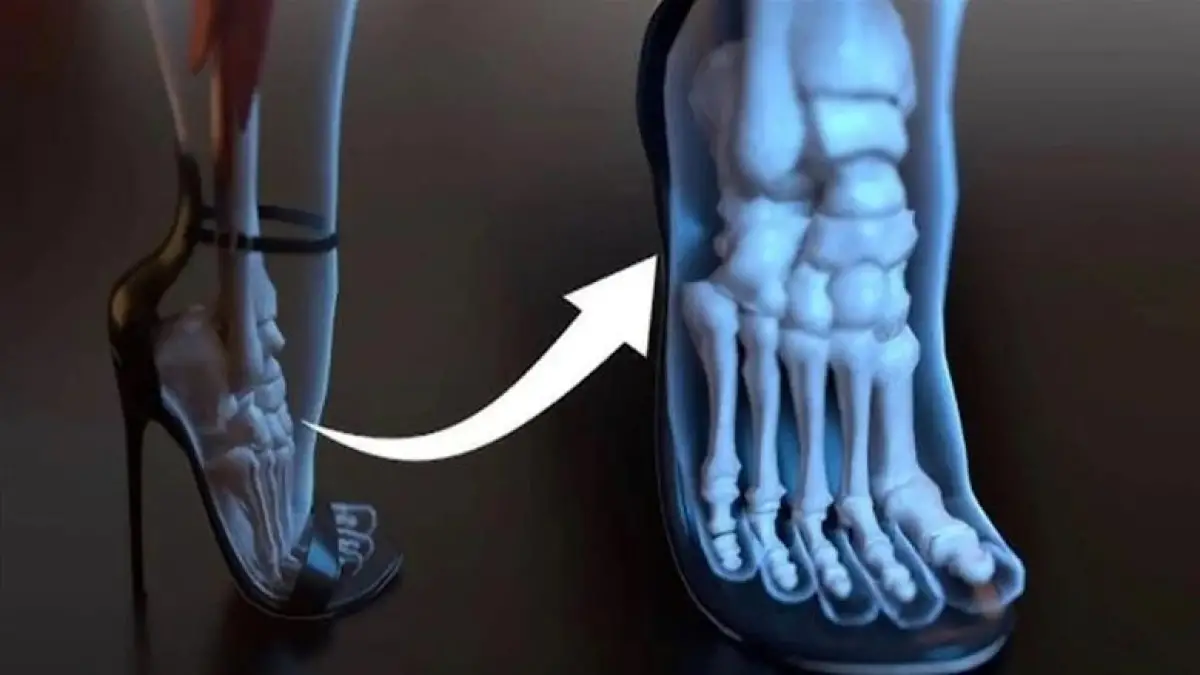

كشفت الدراسات الحديثة التي أجراها استشاريو جراحة عظام القدم والكاحل أن ارتداء الكعب العالي يؤدي إلى تغييرات جذرية في توزيع ثقل الجسم، حيث أظهرت الصور ثلاثية الأبعاد أن القدم تعاني من ضغط هائل وتكدس واضح للأصابع داخل الحذاء؛ الأمر الذي يدفع الإصبع الكبير نحو الداخل ويسبب بروزا عظميا مؤلما يعرف بورم الإبهام، بينما تضطر الأصابع الصغرى للانحناء بشكل قسري في محاولة يائسة للحفاظ على توازن الجسم أثناء الوقوف أو الحركة لفترات ممتدة.

توضح الفحوصات الطبية أن الانتقال من وضعية القدم الطبيعية إلى وضعية الكعب العالي يغير من ميكانيكية الحركة؛ حيث يتركز معظم الوزن على مقدمة المشط مما يضعف الأربطة الحيوية ويقلل من قدرة القدم على امتصاص الصدمات أثناء المشي، وهذا التغيير الهيكلي يتطلب تدخلا وقائيا مستمرا للحفاظ على سلامة العظام وتجنب الجراحات التصحيحية مستقبلا.